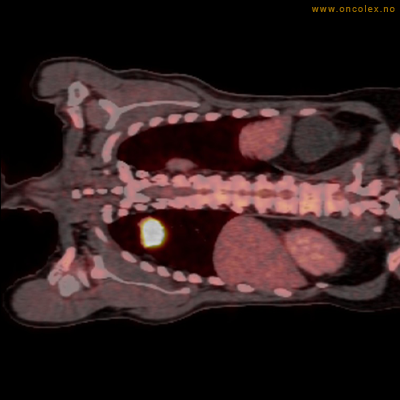

Vev som tar opp mer radioaktivt stoff, synes som hvite områder som lyser opp mer i forhold til annet vev som tar opp mindre sukker.

Kraftig opptak i svulst i lunge.

Lungekreft med spredning til lymfeknute i lungehilus.